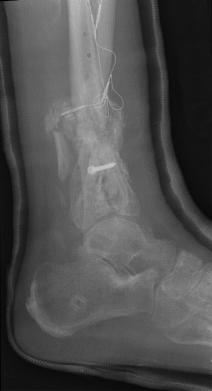

Pre-skin graft & bone infuse surgery X-Rays of the left ankle

These x-rays were taken just prior to surgery where grafts of skin (from Liam's own leg) were used to cover the open wound on Liam's left

ankle. Dr. Gottlieb also took the initiative to infuse material into the tibia gaps (shown in the front ankle view). The infused bone material

should fill in the existing bone gaps and fuse the various bone fragments, resulting in a much stronger support structure. It is hoped that the

3 cm fragment (shown in the side view) will fuse with the other tibia bones as time progresses. No immediate plan exist to modify the remaining

bone fragments / configuration.